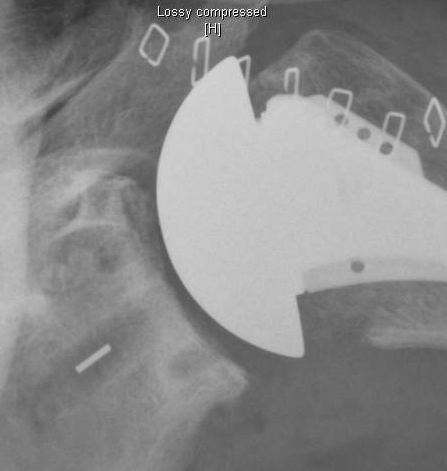

The consistent result is the absence of radiolucent lines with a minimal amount of cement as shown in the radiograph below.